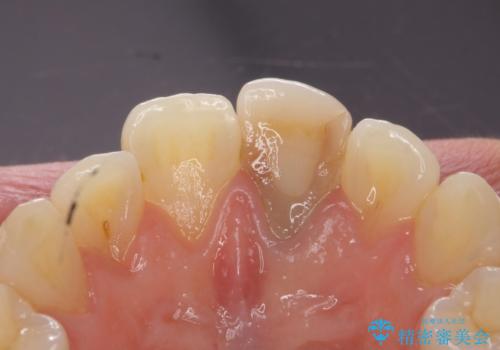

- 前歯の変色を主訴に来院された患者様です。

より審美的な修復を行いたいとのことであったため、ジルコニアクラウンでの修復を行います。

- 左上1 : 仮歯 / 11,000円、ジルコニアクラウン(スペシャル) / 154,000円 合計165,000円(税込)費用は治療当時の料金となります